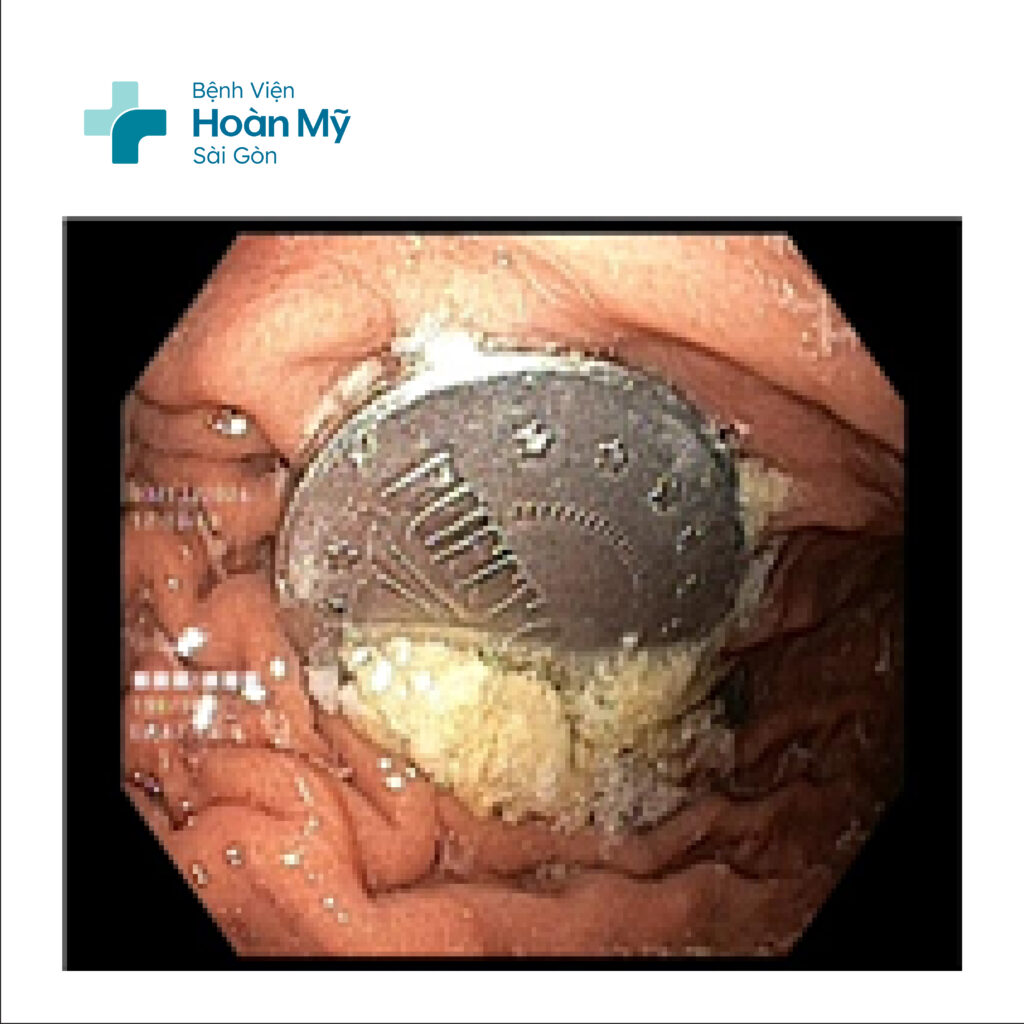

Dị vật nằm trong lòng dạ dày

Do dị vật có bề mặt nhẵn và không có cạnh sắc nhọn nên hạn chế được nguy cơ tổn thương nghiêm trọng đến niêm mạc. Tuy nhiên, việc nội soi can thiệp gắp dị vật vẫn gặp khó khăn do đồng xu có bề mặt trơn và khó kiểm soát, đòi hỏi bác sĩ có kinh nghiệm và thao tác chính xác. Nếu dị vật tiến xuống ruột non, nguy cơ tắc ruột hoặc tổn thương mô sẽ tăng cao, đe dọa đến sức khỏe bệnh nhi.

Dị vật được gắp ra từ dạ dày người bệnh